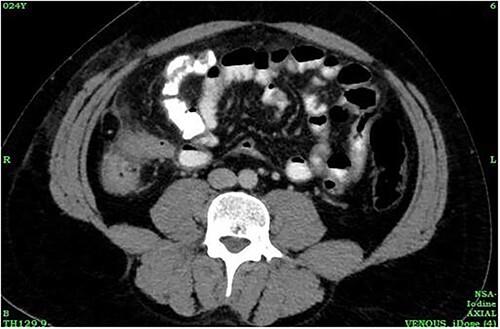

Tuberculosis (TB) remains as a significant global public health issue, especially in developing and underdeveloped nations. Extrapulmonary TB comprises 20% of the TB cases; of which 34.4% were in the lymphatics, 25.2% pleural, followed by 12.8% gastrointestinal and 9.4% in the central nervous system. Ileocecal involvement is the most common among gastrointestinal TB. Although it can cause secondary damage to the appendix, primary type of appendicular TB is rare and can occur with no other signs of the disease. A high index of suspicion is necessary for early diagnosis and treatment of TB. Similarly, stump appendicitis (SA) is a rare and delayed complication of appendectomy. Here we report a case of primary appendicular TB in a patient presented to a multi-specialty hospital in Kerala, India, with SA.

结核病(TB)仍然是一个重大的全球公共卫生问题,尤其是在发展中国家和不发达国家。肺外结核占结核病病例的20%;其中34.4%发生在淋巴管,25.2%在胸膜,其次是12.8%在胃肠道,9.4%在中枢神经系统。回盲部受累是胃肠道结核中最常见的。虽然它可导致阑尾继发性损害,但原发性阑尾结核很少见,且可在无其他疾病体征的情况下发生。对于结核病的早期诊断和治疗,高度的怀疑指数是必要的。同样,残端阑尾炎(SA)是阑尾切除术后一种罕见的延迟并发症。在此,我们报告一例原发性阑尾结核患者的病例,该患者在印度喀拉拉邦的一家多专科医院就诊,患有残端阑尾炎。